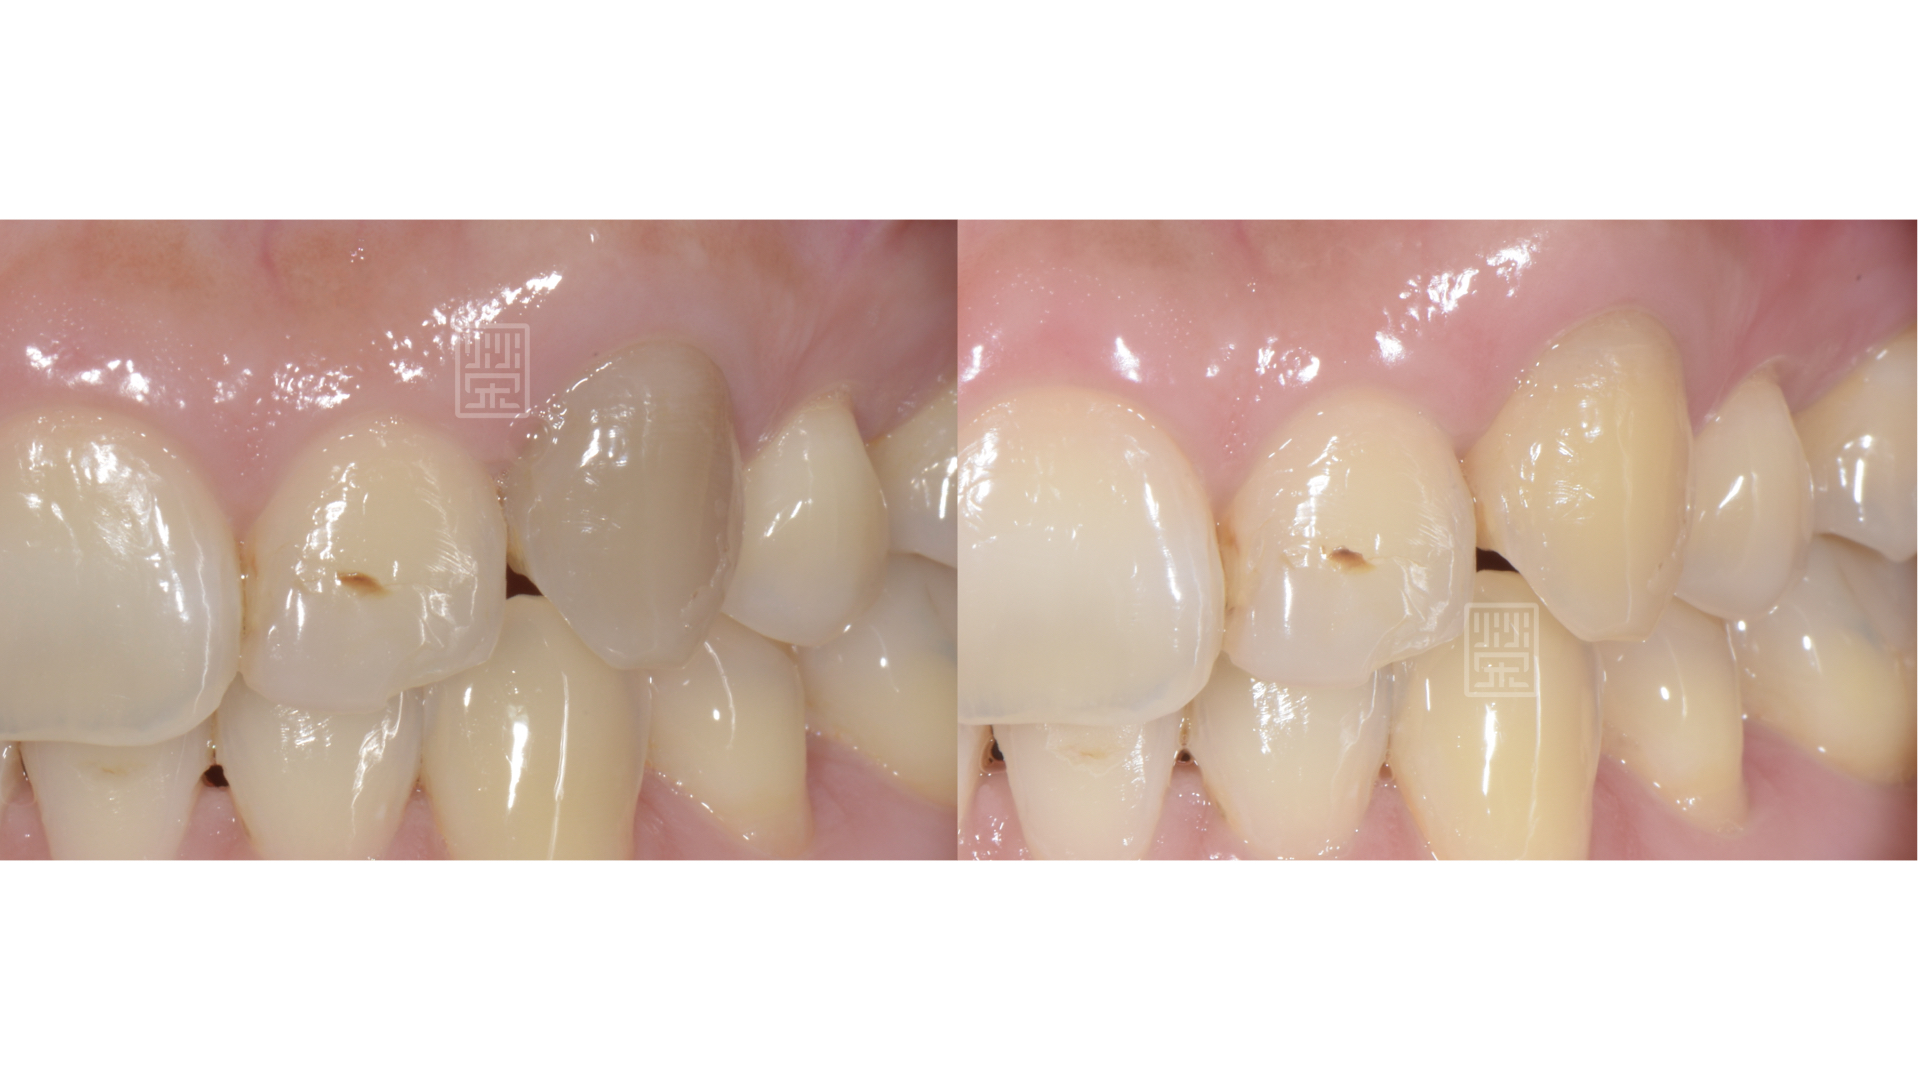

犬齒變灰黑色

根管治療並且齒內美白

牙齒恢復顏色